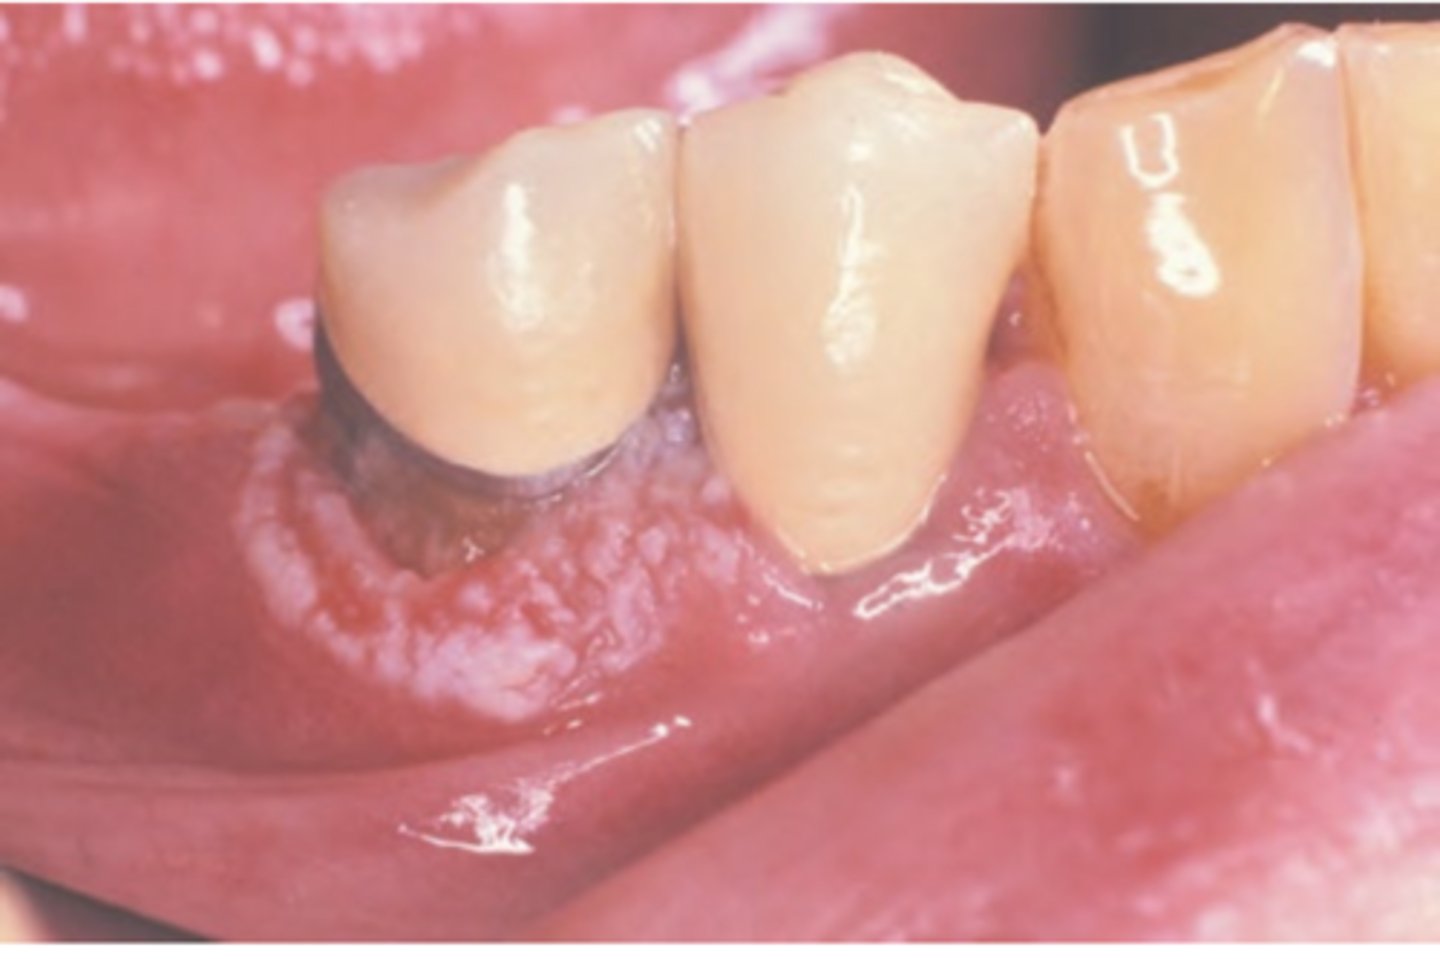

Squamous Cell Carcinoma (gingival and alveolar)

Hint: mimics common, benign inflammatory and reactive lesions (pyogenic granuloma)